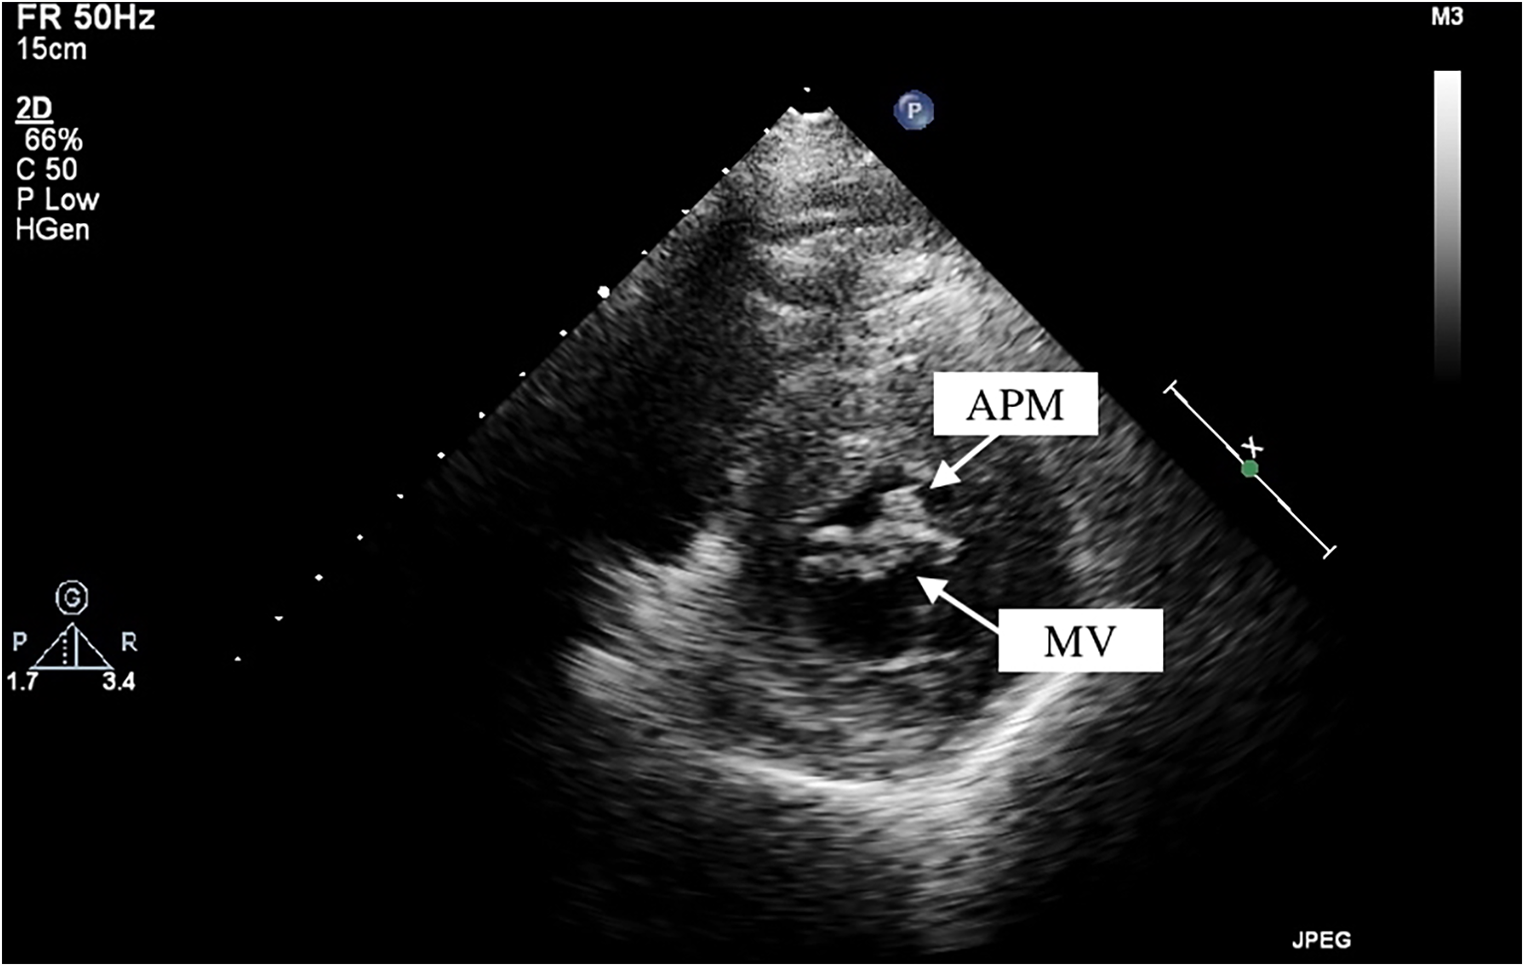

Among these patients with HOCM, two cases of APM insertion were preoperatively detected using transthoracic echocardiography, with a sensitivity of 25%. CT was performed in seven patients, and MRI was available for six patients. However, only two and one cases of APM insertion were operatively detected, leading to sensitivities of 28.6% and 16.7% for CT and MRI, respectively. By reviewing the echocardiographic images, we observed a particular feature of APM insertion: the APM adhering to the leaflet looked like a lip nevus in the horizontal cross-section (Figure 2 and Supplementary Video S1). By contrast, Supplementary Video S2 shows the echocardiography findings for HOCM without APM insertion. The “lip nevus sign” was found in 62.5% (5/8) of patients.

Figure 2

Anomalous papillary muscle (upper arrow) insertion into the mitral valve (lower arrow) visualized by transthoracic echocardiography. APM, anomalous papillary muscle; MV, mitral valve.